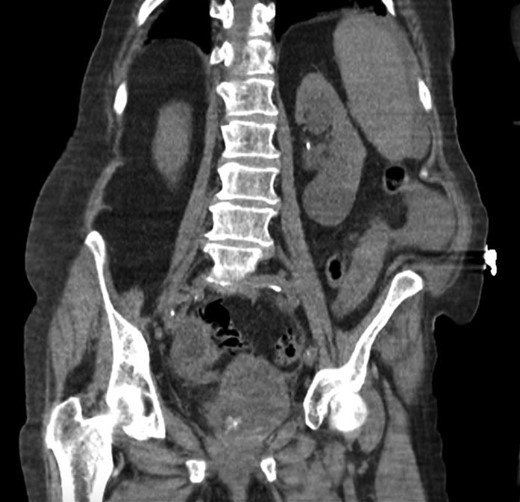

She was a former smoker with past medical history of hypertension, cerebrovascular event, hypothyroidism, and hyperlipidemia, and esophagogastroduodenoscopy and colonoscopy for gastrointestinal bleed, without past surgical history. On physical exam, she was normothermic, tachycardic, hypotensive and saturating 100% on room air. She had a distended, diffusely tender abdomen with guarding and rebound tenderness. Laboratory results were notable for leukocytosis with a left shift, chronic anemia, and acute kidney injury. Computed tomography of the chest, abdomen, and pelvis showed esophageal thickening, free air under the diaphragm, duodenal inflammation, generalized mesenteric fat stranding, free fluid in the abdomen and pelvis, and a thickened and inflamed bladder wall with irregular foci of hyperintensity within the bladder lumen and a left hydroureteronephrosis (Figs 1–3).

Coronal computed tomography showing a thickened inflamed bladder wall and irregular foci of hyperintensity within the bladder lumen.